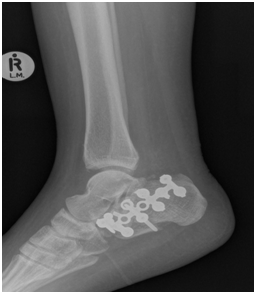

Radiologically

The calcaneus fracture has healed with no Talar shift or tilt (Figure 7-9).

Figure 7 X-Ray of right Ankle: shows no Talar tilt, shift or syndesmotic diastasis.

Figure 8 Lateral view of the ankle: shows the maintained post op position of the tibia and fibula over the talus. The image also shows the healed Calcaneus fracture post ORIF.

Figure 9 Mortise view of the right ankle: shows once again no Talar tilt, shift or syndesmotic diastasis. The ankle joint is congruent.